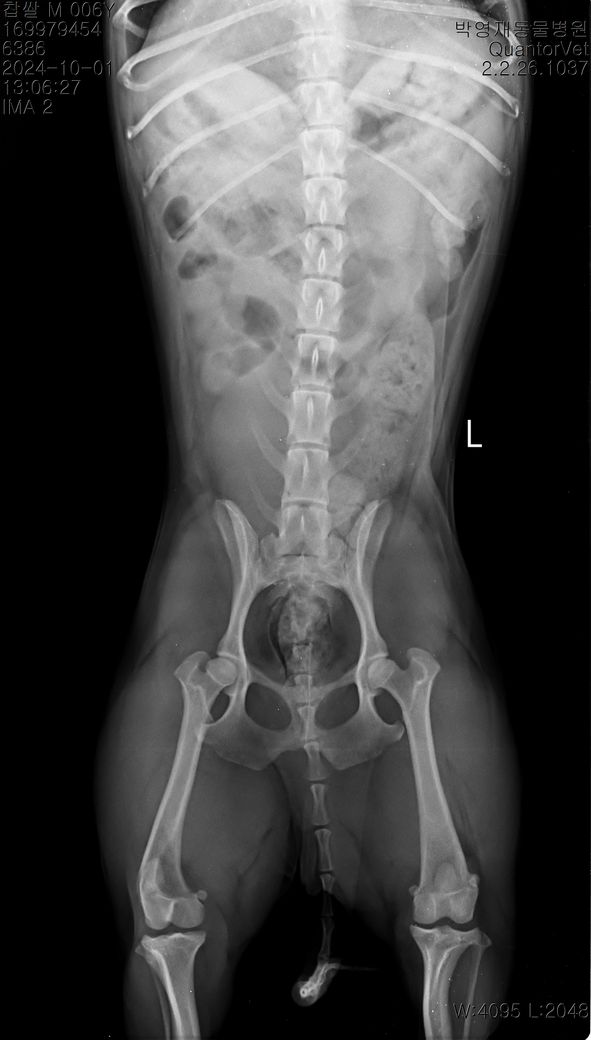

현제 6살 3개월 남자 중성화 되어있는 5.6kg 비숑 입니다,

1살 6개월쯤 뛰다 미끄러져 병원 내원 했을때 십자인대 부분단열 의심.탈구 1기 진단 받았고

3주전쯤 흥분해 뛰다 턴하면서 악소리를 크게지르고 주저 앉았다 다리를 들고 있었고 수분뒤엔 다시 잘 걸었습니다. 다음날 병원 내원 엑스레이,촉진상 근육이 좋아서 탈구도 약간있고 십자인대 가 좀 좋진 않지만 당장 수술할정도는 아니라 들었습니다. 근데 그뒤로 집에서 걷다가도 밖에서 뛰다가도 하루 한두번씩 그래요.